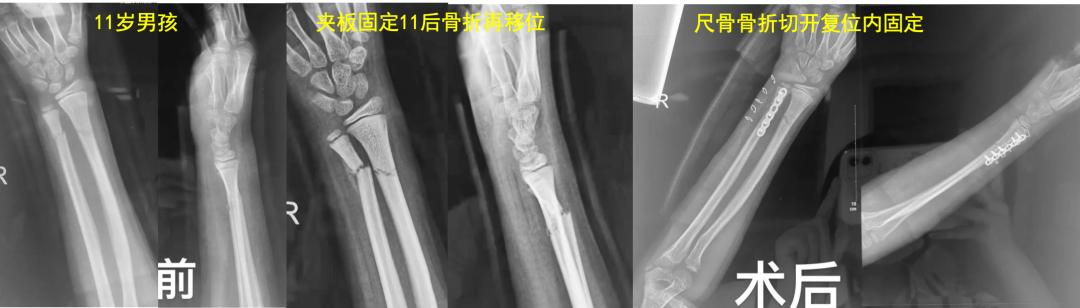

学生: 这两天有两个儿童前臂骨折的病例在骨科同行中引发很大的争议,几乎是一边倒的指责“治疗不当”。一例是11岁的男孩,摔伤后前臂远端骨折,夹板固定11天后再移位,医生做了切开复位内固定。另一例是摔倒致伤的6岁孩子,医生做了微创“创新”的外固定架固定手术,您怎么看?

老师: 下面两个病例,分别是9岁4个月男孩的前臂中段骨折,保守治疗后3个月骨折对位、愈合良好。另外一个12岁男孩,早期外院保守治疗,三周时骨折再移位,于我院再次整复后恢复满意。